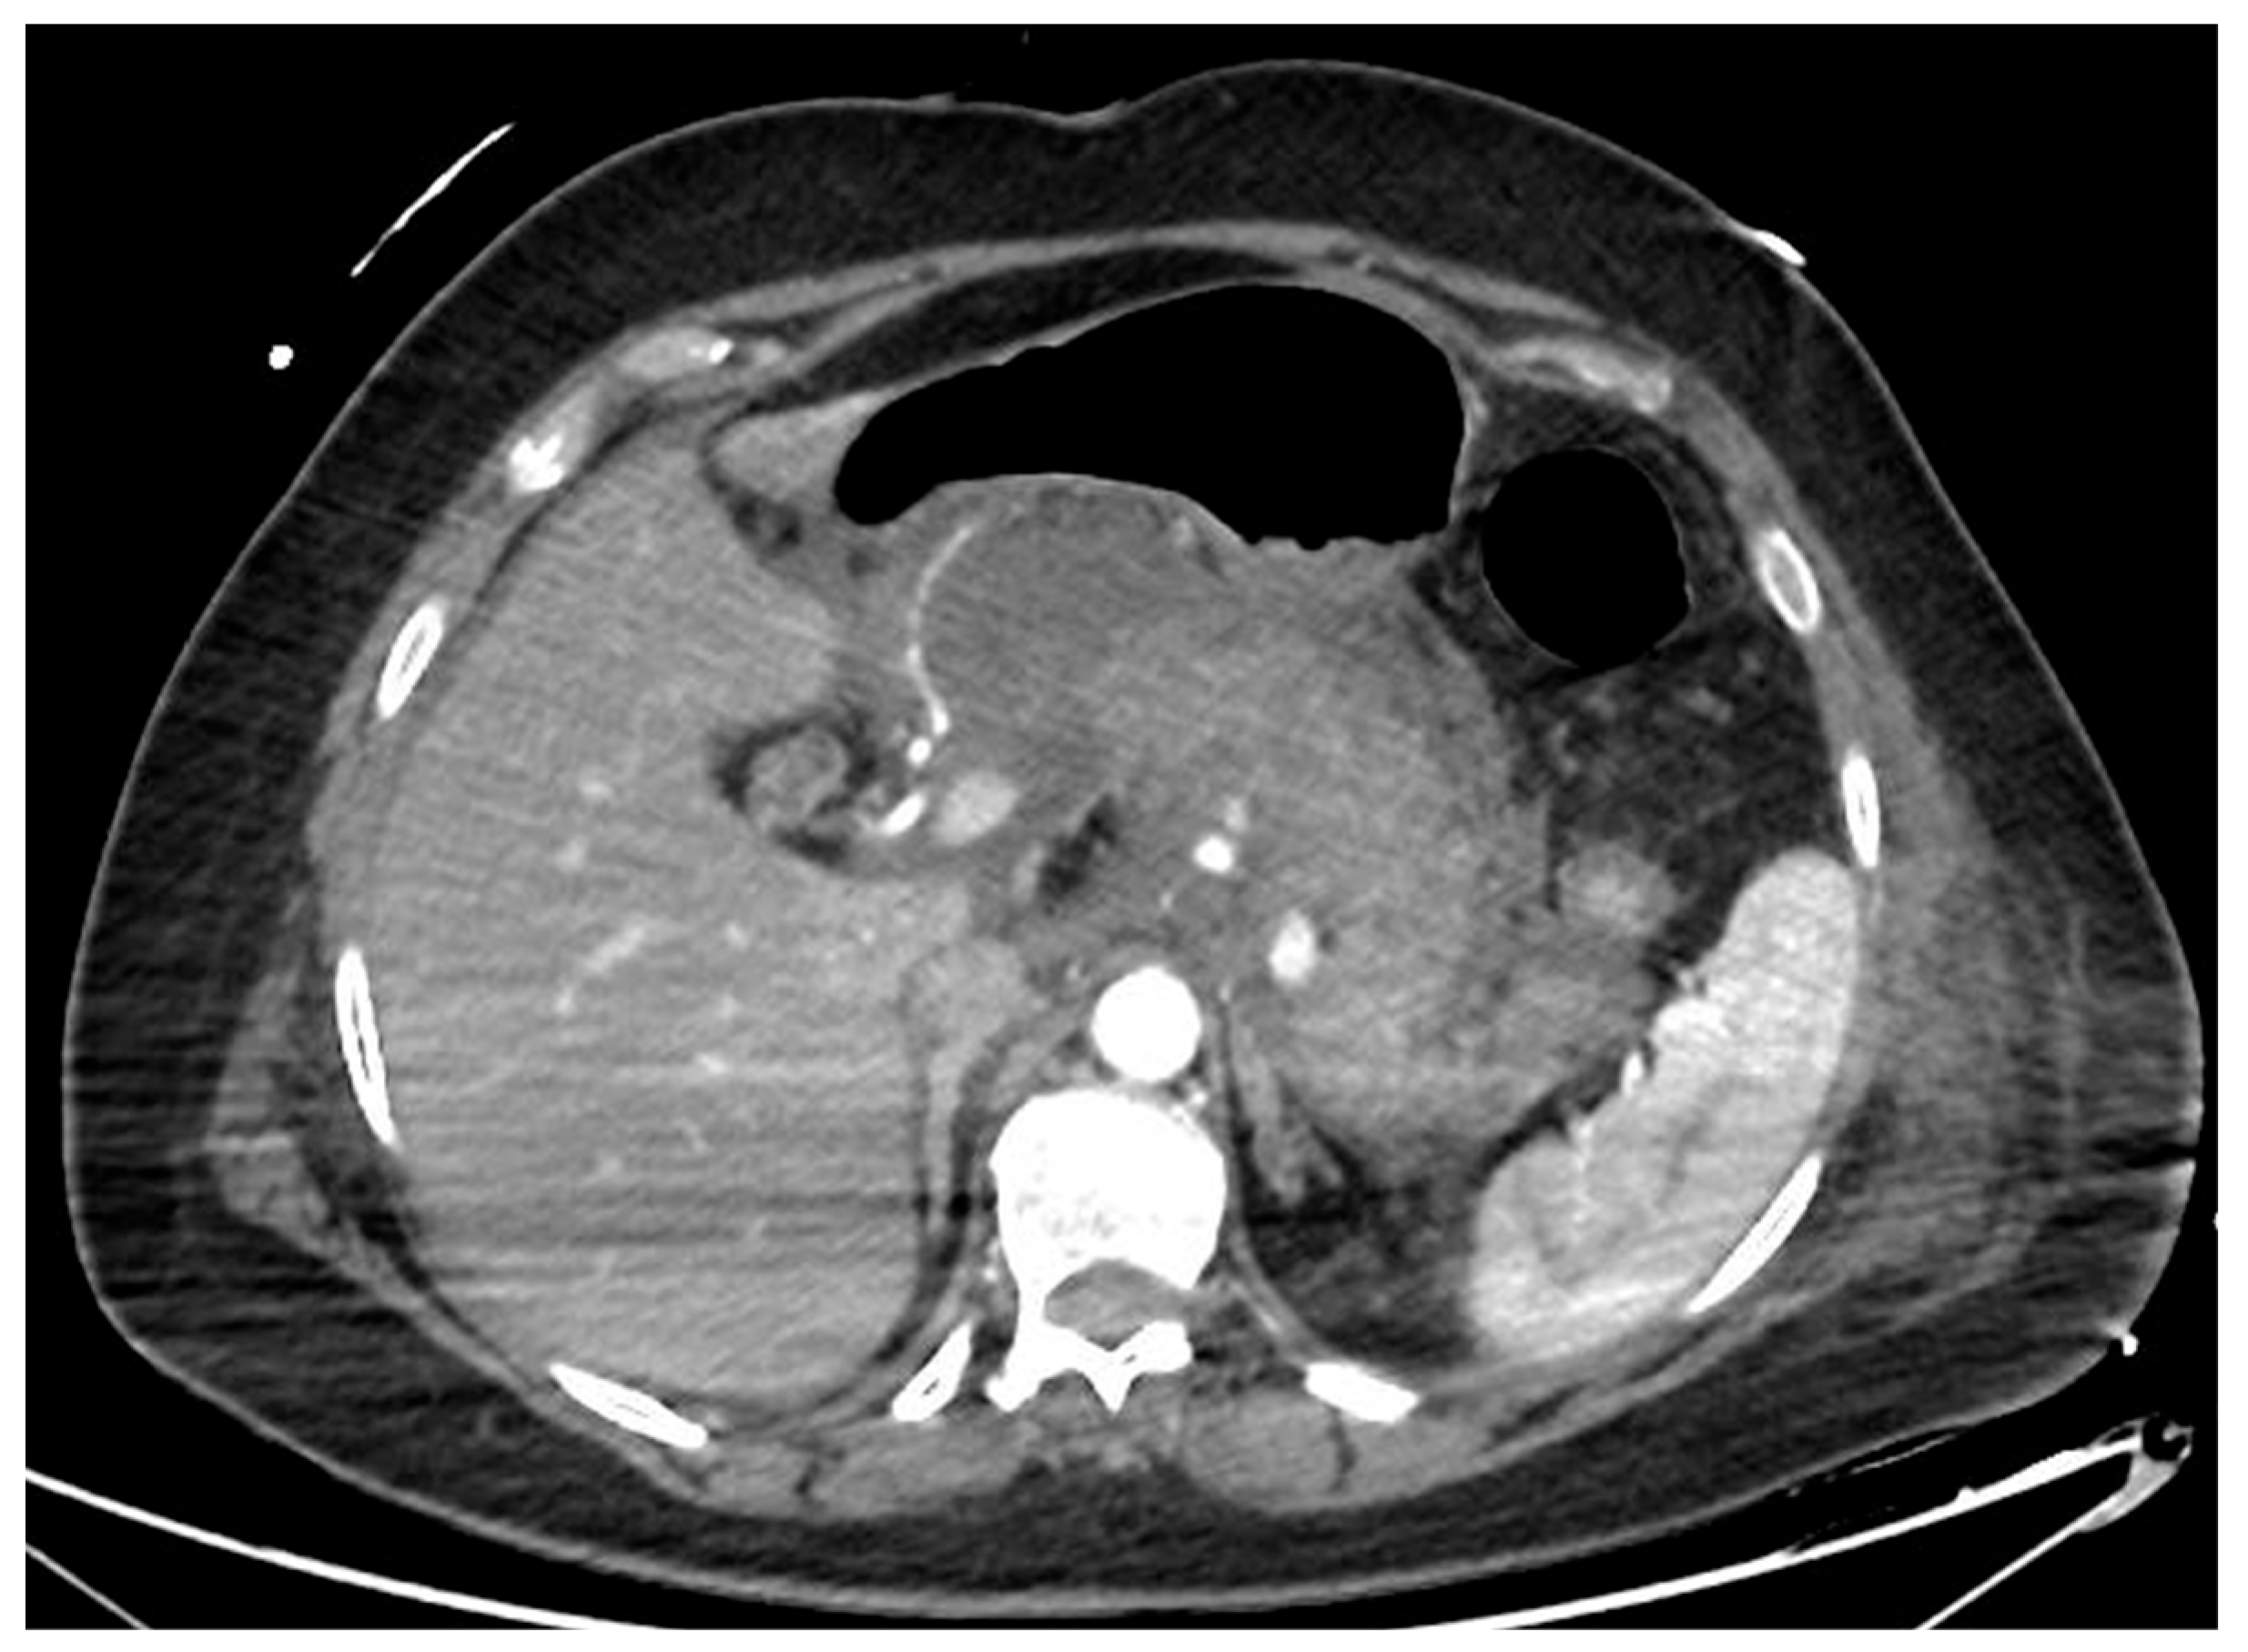

Figure 1.

CT scan image of a necrotizing pancreatitis, with hypoenhancing areas of pancreatic parenchyma. CT, computed tomography.